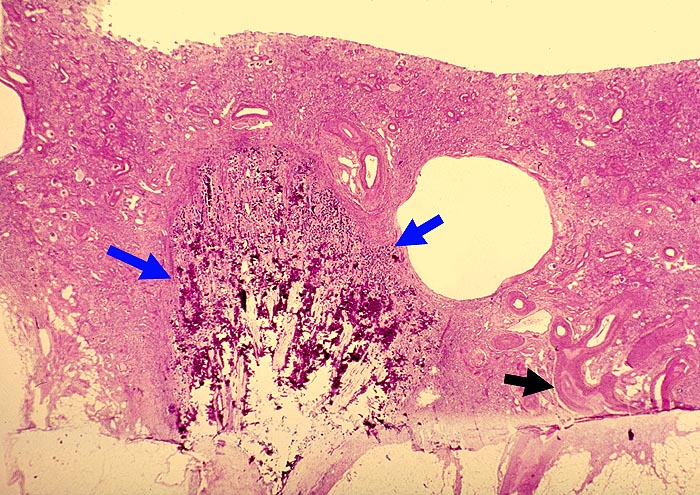

Verknöcherte Papillennekrose bei Analgetikanephropathie

Hochgradig geschrumpfte Nierenrinde. Die Tubuli sind vollständig atroph. Die gesamte nekrotische Papille ist in situ verblieben verkalkt und verknöchert. Die Gefässe zeigen eine ausgeprägte adaptative Intimafibrose.